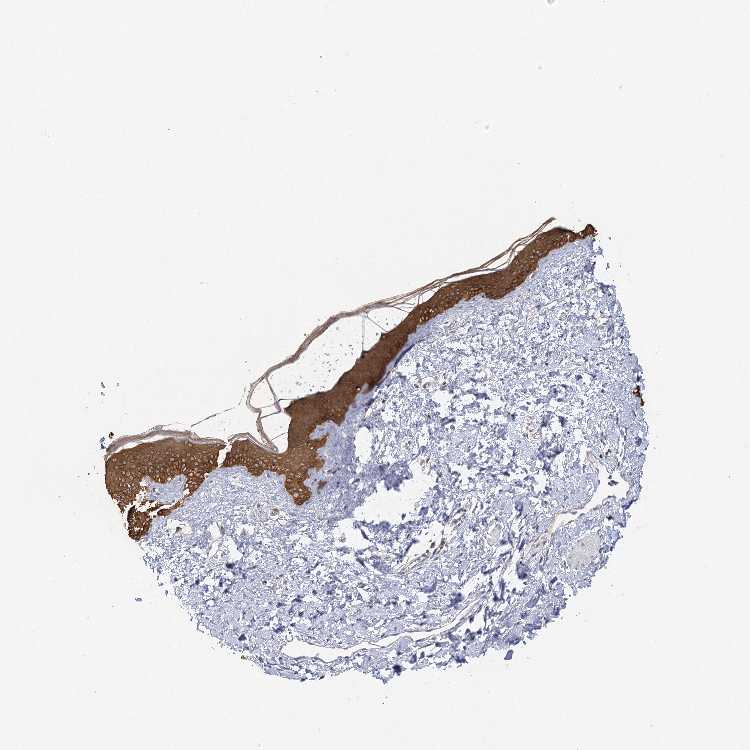

SKIN 1 - Antibody stainingi

Antibody staining in the annotated cell types in the current human tissue is reported as not detected, low, medium, or high, based on conventional immunohistochemistry profiling in selected tissues. This score is based on the combination of the staining intensity and fraction of stained cells.

Each image is clickable and will lead to virtual microscopy that enables deeper exploration of all samples and also displays staining intensity scores, fraction scores and subcellular localization as well as patient and tissue information for each sample.

Antibody HPA013162Antibody HPA036652Antibody CAB032830

Langerhans Medium-Medium

Cells in basal layer -Medium-

Cells in corneal layer -Not detected-

Cells in granular layer -Medium-

Cells in spinous layer -Medium-

Eccrine glands -Medium-

Endothelial cells -High-

Extracellular matrix -Not detected-

Fibroblasts Not detected-Medium

Fibrohistiocytic cells -High-

Hair follicles -Medium-

Keratinocytes Medium-Medium

Langerhans cells -Medium-

Lymphocytes -High-

Melanocytes LowHighHigh

Sebaceous glands -Medium-

Vascular mural cells -Not detected-